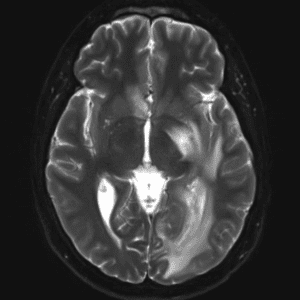

Case #10

Intraventricular meningioma